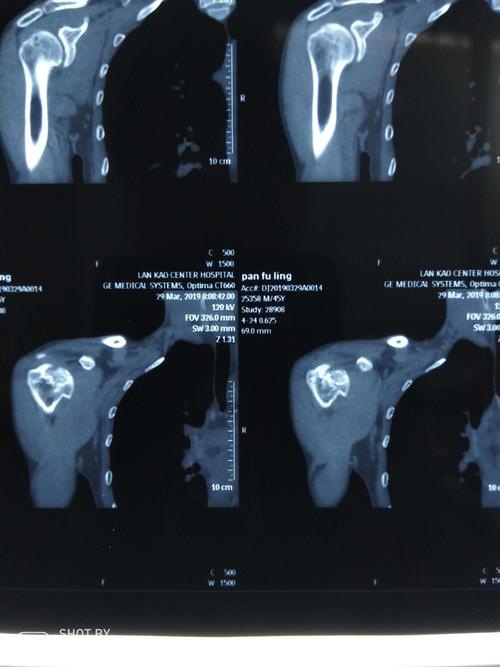

该患者行ct检查提示肩关节后脱位合并反bankart损伤 反hill-sachs

右肩ct

水平位ct显示肱骨头后脱位.